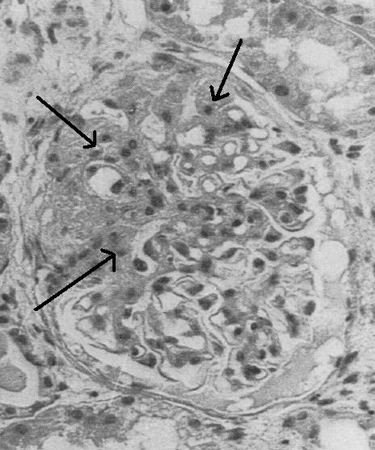

FSGS is characterised on light microscopy by focal segmental areas of mesangial collapse and sclerosis.

Morphological categories are perihilar variant, cellular variant, collapsing variant, tip variant, and not otherwise specified.

Immunofluorescence microscopy is usually unremarkable.

Electron microscopy can distinguish primary from secondary FSGS. Foot process fusion is diffuse in primary FSGS but is mostly limited to sclerotic areas in secondary FSGS.[Figure caption and citation for the preceding image starts]: Light microscopy of renal biopsy showing typical lesions of focal segmental glomerulosclerosisAdapted from Nagi AH, Alexander F, Lannigan R. Light and electron microscopical studies of focal glomerular sclerosis. J Clin Pathol. 1971 Dec;24(9):846-50 [Citation ends].

Result

focal segmental areas of mesangial collapse and sclerosis